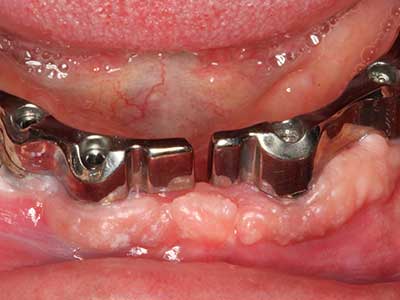

When surgical procedures are performed on bone in the immediate vicinity of sensitive structures such as blood vessels or nerves, rotary instruments pose a significant risk of iatrogenic injury. Piezoelectric devices can be helpful for preparation of bone covers and removal of hard tissue close to nerves, particularly for exposure of nerves after iatrogenic injury but also during nerve lateralization for resective and reconstructive procedures or implant placement (Fig. 17-20). Light contact between the piezotip and the nerve does not generally result in damage but proceeding incautiously with saw-like motions or attachments where a residual bone substrate remains may cause temporary or even permanent nerve damage. However, the risk of damage is considered to be substantially lower than when using saws or milling instruments (Pereira, Gealh et al. 2014).